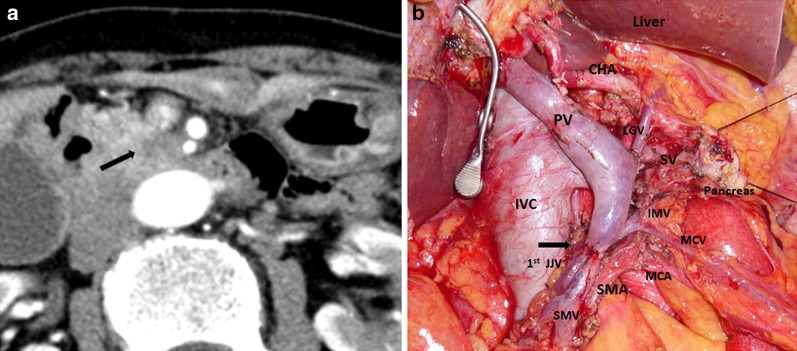

Fig. 2.

Postoperative contrast-enhanced computed tomography (CECT) evaluation. a CECT on postoperative day 14 shows intrahepatic portal thrombosis (black arrow) and edema of the Glissonian pedicle, while the superior mesenteric vein anastomosis was patent without thrombosis. b No evidence of intraperitoneal infection, such as pancreatic fistula or bile fistula, was observed. The black arrow indicates the remnant pancreas